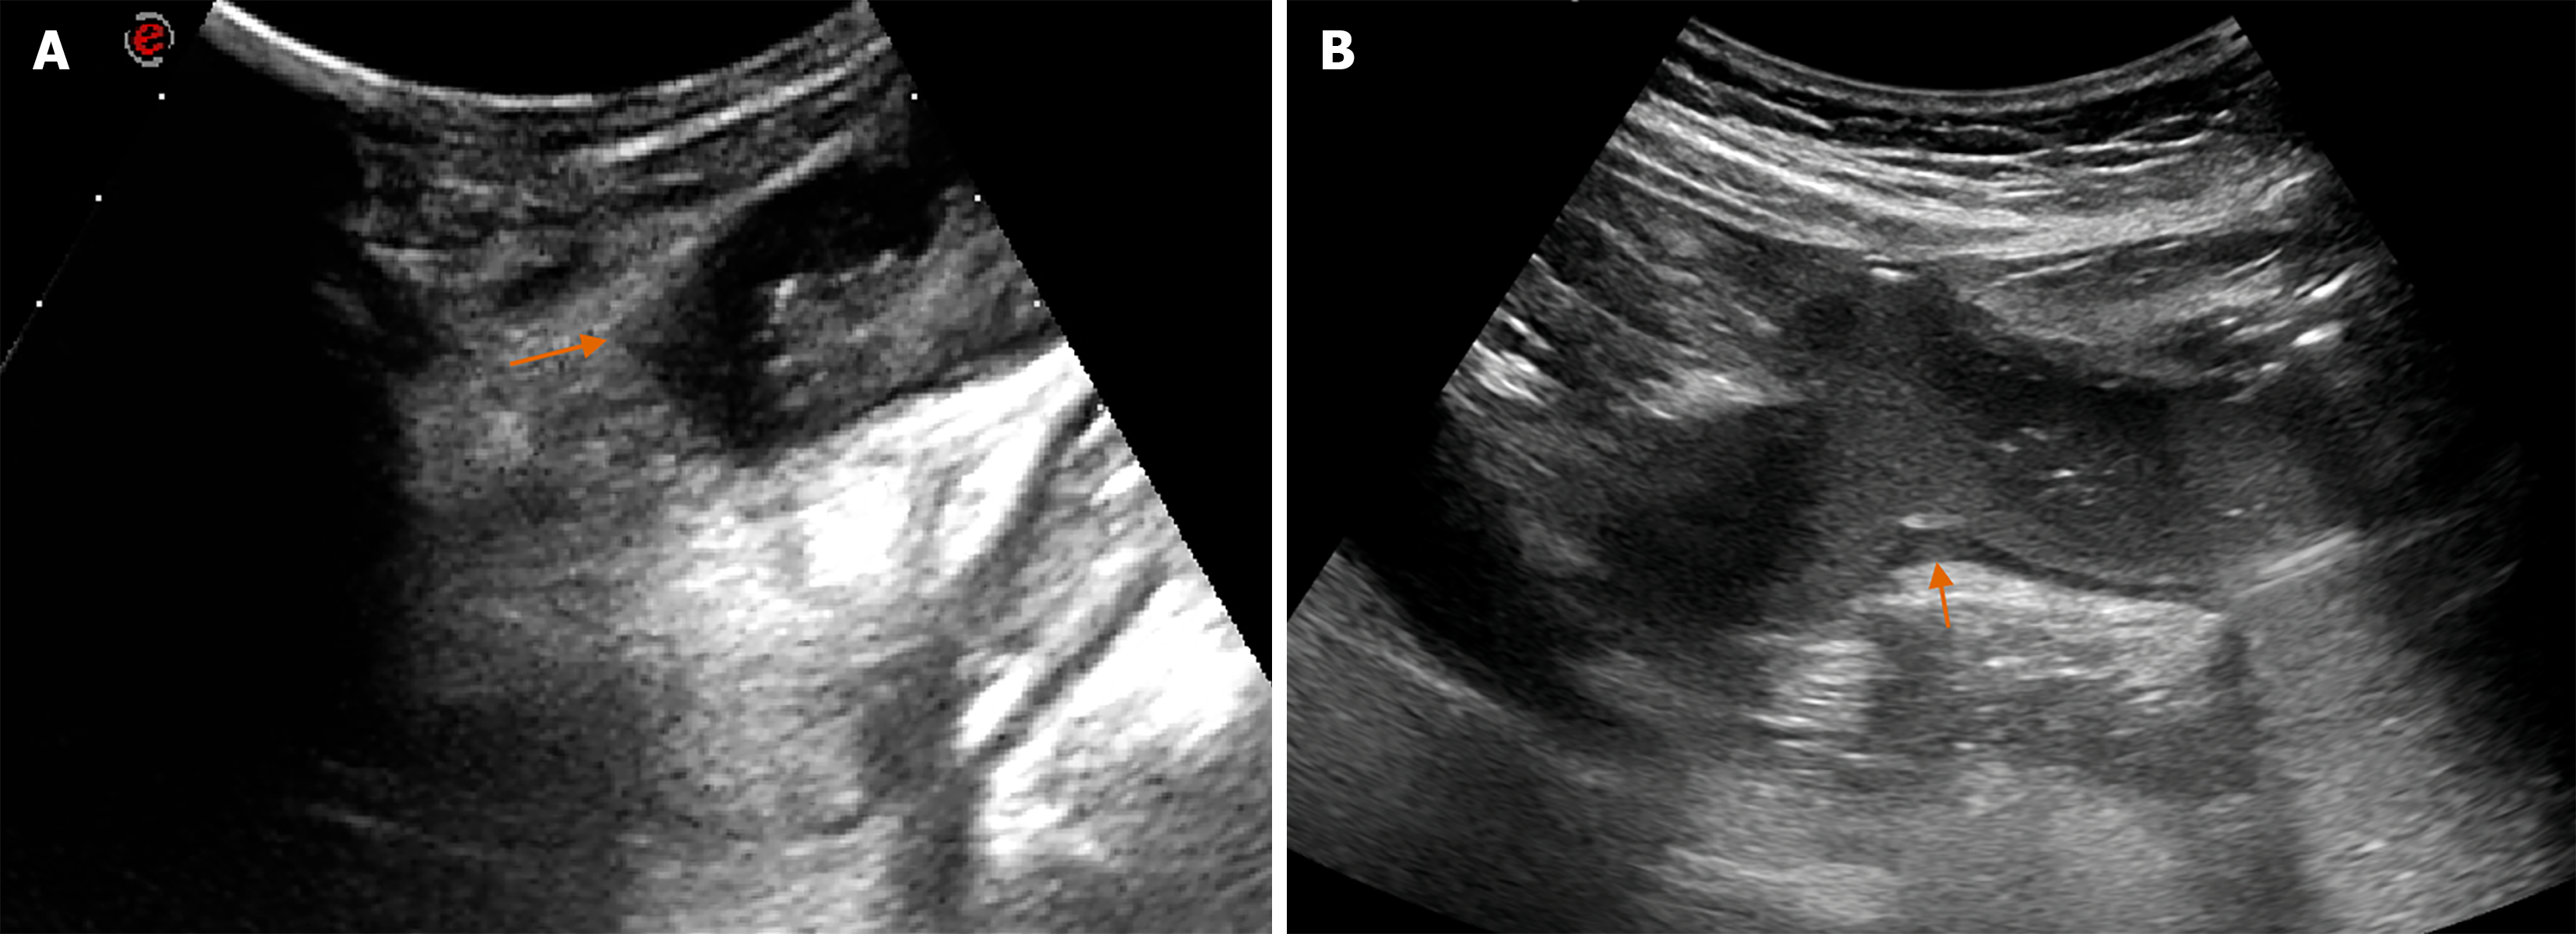

Figure 2 Imaging features of lesions with and without angle sign on transabdominal ultrasound.

A: T4a staging of gastric cancer (GC) lesion with an angle sign, which showed that hypoechoic intrinsic muscular layer protruded outward to form an angle (red arrow); B: T2 staging of GC lesion without an angle sign.